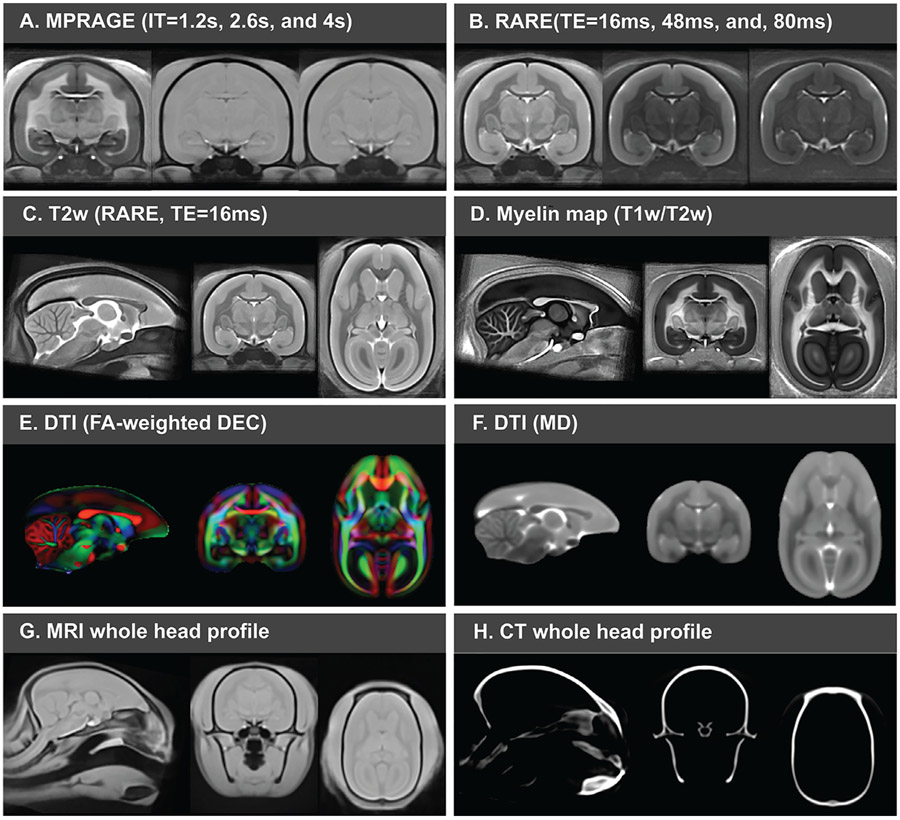

We constructed multimodal population-averaged templates by using the Multivariate Template Construction method of ANTs (for MRI and CT data) and the tensor-based method of the TORTOISE software (for DTI data). The template set includes multiple modalities (Fig. 3). The MP3RAGE (TI = 1200 ms) provides T1w contrast (Fig. 3A), and the other TIs (TI = 2600 ms and 4600 ms) can be used for the registration of images with low contrast. With different effective TEs, we provide templates with varying levels of T2w contrast (Fig. 3B). We can estimate the T1 map based on the multi-TI MP3RAGE images and the T2 map on multi-echo RARE images, respectively. Based on the ratio between T1w and T2w images, we generated the “myelin map” template, which enhances contrasts between the GM and the WM (Fig. 3D). The diffusion tensor template allows for tensor-based registration and can generate multiple DTI contrasts, such as fractional anisotropy (FA) and mean diffusivity (MD) (Fig. 3E and F). Also, we include two types of large FOV whole head template: one is MRI-based (Fig. 3G), and the other is CT-based (Fig. 3H). The rich template modalities facilitate a wide range of neuroimaging applications, as we can choose the matched template contrast for spatial normalization.

Fig. 3. Multi-modal population-based standard templates.

The standard templates include the MP3RAGE with TI = 1.2 s (T1w contrast), 2.6 s, and 4 s (A), RARE with TE = 16 ms, 48 ms, and 80 ms for different T2w contrasts (B and C), myelin map (T1w/T2w), contrasts from diffusion tensor images (E and F), the MRI whole head profiles (G) and CT whole head profiles (H).